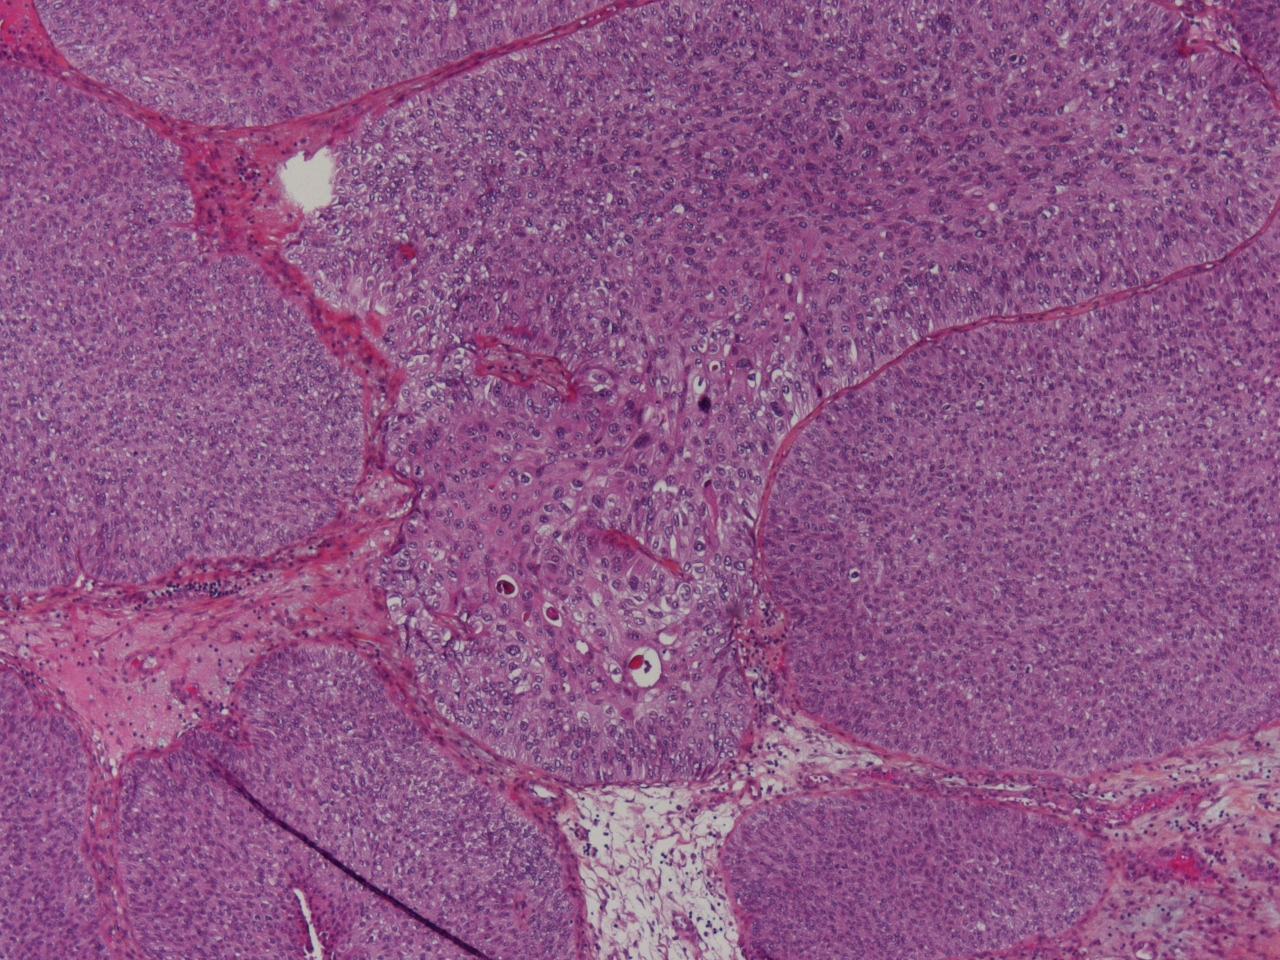

Bladder Papillary Lesions

Case ID: 475